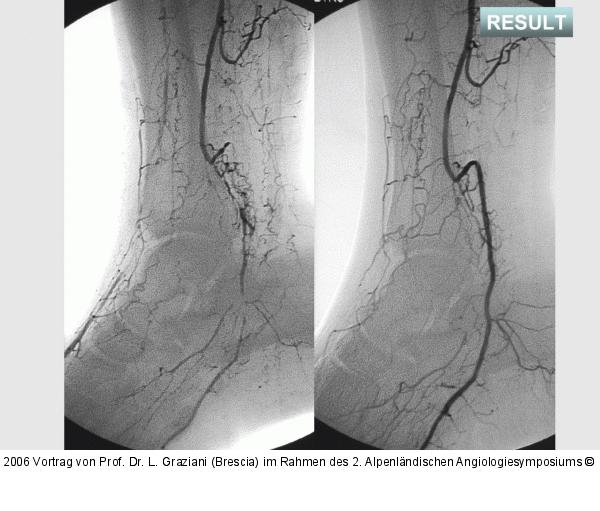

Abbildung 76: Arteria dorsalis pedis - Katheterisation

Arteria dorsalis pedis - Katheterisation